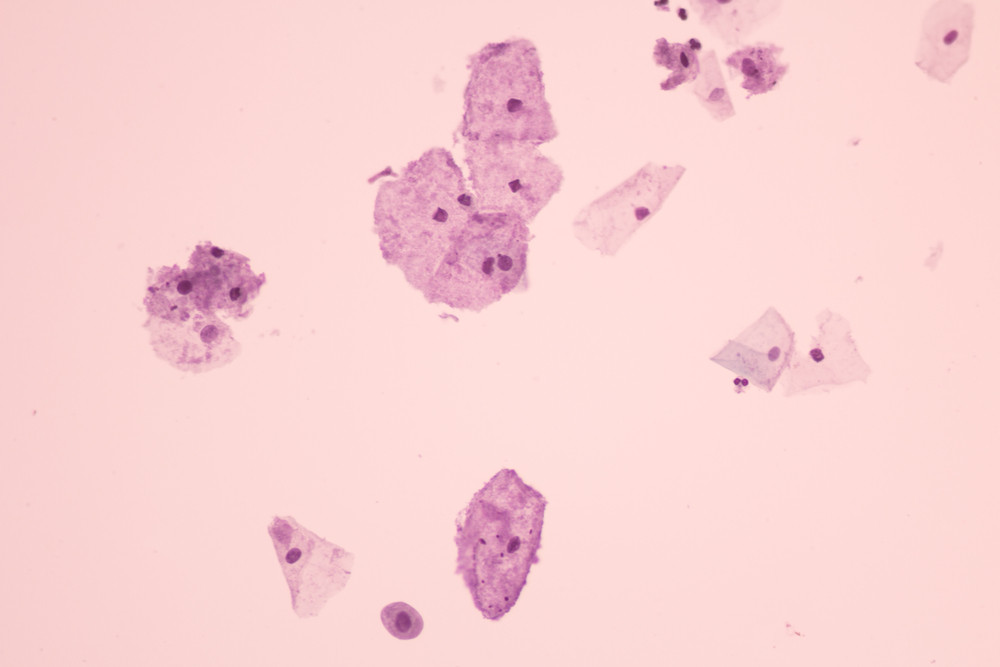

Врачи выделяют три степени патологии. Они определяются по составу микрофлоры при микроскопическом исследовании:

- Компенсированный. Полезных лактобактерий стало меньше, но вредные микробы пока не размножились слишком сильно. Однако риск их роста повышен.

- Субкомпенсированный. Лактобактерий уже мало, а условно-патогенных бактерий становится больше, чем в норме. Это приводит к появлению первых неприятных симптомов.

- Декомпенсированный. Полезные бактерии почти полностью исчезают, а вредные активно размножаются. На этом этапе женщина испытывает выраженный дискомфорт: появляются неприятные выделения, зуд, жжение, неприятный запах.

- Мазок на флору. Покажет, какие бактерии есть, есть ли воспаление и нарушен ли баланс.